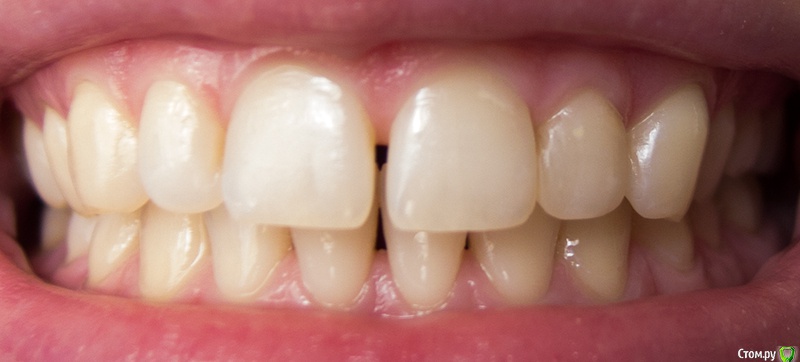

ptichka Опубликовано 1 марта, 2015 Поделиться Опубликовано 1 марта, 2015 ЗдравствуйтеМне 34 года.Беспокоит субъективно продолжающееся уменьшение межзубных сосочков между нижними резцами (впервые заметила около 10 лет назад) - особенно центральными, и по чуть-чуть между центральным и боковым резцом на обеих челюстях.Эта проблема почти не заметна в жизни, т.к. промежуток заполняется слюной и отсвечивает.Зубы не шатаются, зубного камня нет (то есть он не образуется). Имеет ли смысл делать рентген и т.п. Если межзубные промежутки действительно атрофируются, есть ли какое-то лечение в данный момент? Если какой-то способ сделать десневой сосочек более объемным в чисто косметических целях? Ссылка на комментарий

krokomot Опубликовано 2 марта, 2015 Поделиться Опубликовано 2 марта, 2015 Судя по снимку и фотографиям у вас все в порядке, разве что чистите неправильно зубы. Беспокоится особенно не о чем. 1 Ссылка на комментарий

ptichka Опубликовано 4 марта, 2015 Автор Поделиться Опубликовано 4 марта, 2015 У вас неправильное представление о качествевенной стоматологии и о том что коронки =запах+воспаление. Не надо паниковать. Снимки в студию. На все ваши вопросы пусть ответит ваш стоматолог, у которого будете лечиться Извините, что отнимаю у Вас время, но насколько я понимаю, десна не может так же плотно прилегать к коронке, как к родному зубу. Если я не права, то почему после пломбировки кариеса под десной десны прилегают к пломбе хуже, вот например десневой сосочек между центральным и боковым резцами верхней челюсти слева после установки пломб у меня выглядит менее эстетично, чем справа (хотя пломбы хорошо и неоднократно заполированы). Я и в самой теме написала, что меня больше всего пугает ситуация возможных проблем с деснами. Просто, если Вас не затруднит, объясните мне доступным языком: зачем мне сейчас делать снимки этих зубов и (возможно) их перелечивать? Если бы не этот диалог, мне бы ещё и 10, и 20 лет не пришло бы в голову это сделать. Чем это грозит, никто не ответил. Заражение крови, внезапная смерть? Ну у меня должна же быть мотивация. Ссылка на комментарий